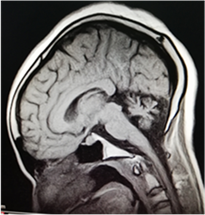

Brain Magnetic Resonance Imaging (MRI) shows cerebellar hypoplasia with normal cerebrum and brain stem (Figure 1(a) and Figure 1(b)).

(a) (b)

Figure 1. Brain MRI of the patient showing cerebellar hypoplasia with normal cerebrum, brain stem and ventricle. Informed consent was obtained from the patient to allow data and image publication.

The absence of an affected family member could suggest that the index case is probably sporadic. The hypergonadotropic hypogonadism with cerebellar ataxia can be associated with many other neurological disorders. These include sensorineural deafness, also called Perrault Syndrome, late-onset with a dominant mode of inheritance [14] . Her ability to complete her tertiary education showed that the index patient had a good level of intelligence before the decline in cognitive function commenced. Cognitive decline is considered one of the key features of GDHS [15] . Brain imaging showed pure cerebellar hypoplasia; the cerebral hemispheres were normal. The hormone profile showed hypergonadotropic hypogonadism with a normal thyroid axis and this was also reported by different authors [15] .